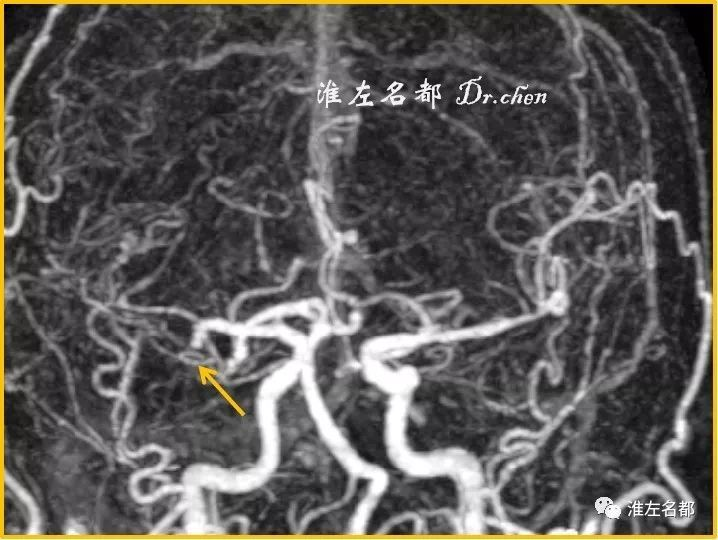

△TOF-MRA:右侧MCA近端闭塞